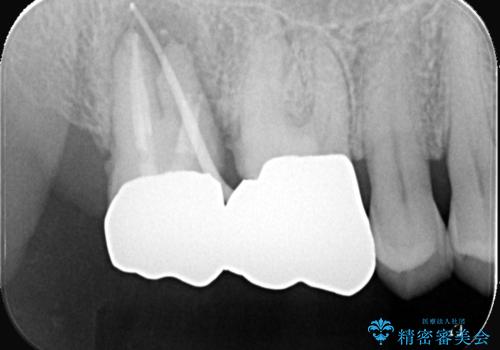

- 当院にて根管治療を行いましたが、病変の改善が得られなかったため、インプラント治療を行う方針といたしました。

抜歯即時埋入の適応と判断し、抜歯当日にインプラント埋入を行う「抜歯即時埋入」にて処置を実施しました。

●治療期間の短縮

抜歯とインプラント埋入を同時に行うため、抜歯窩の治癒を待つ必要がなく、全体の治療期間を短縮できる。